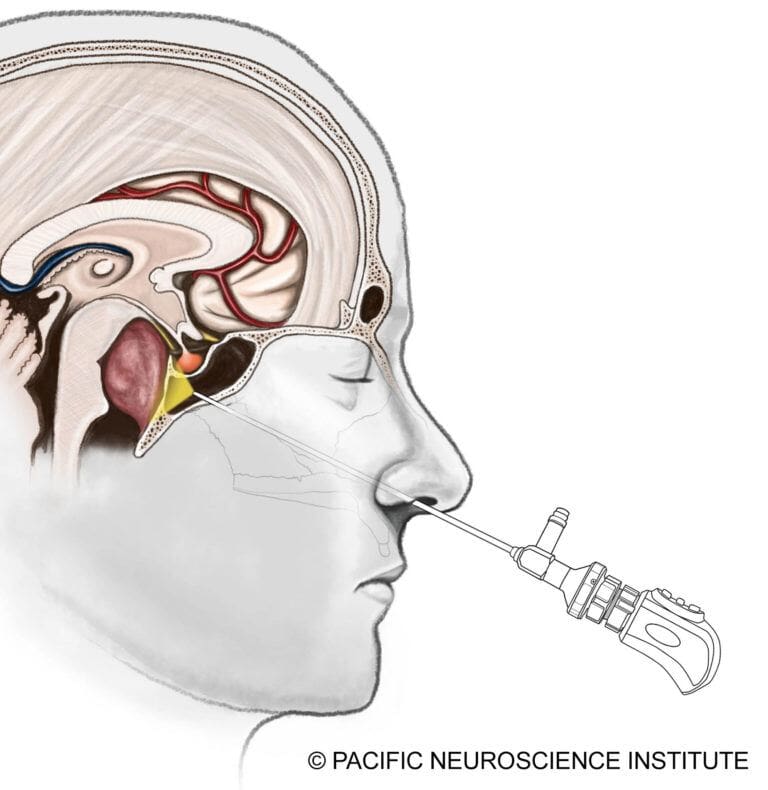

The gold standard for chordoma treatment is surgical resection of the tumor. Most skull base chordomas are midline tumors and are best approached through a minimally invasive approach such as an endoscopic endonasal transclival approach through the nostrils.

Tumors with lateral extension may require alternative or combined approaches, such as a retrosigmoid craniotomy from behind the ear. The goal is maximal safe resection, prioritizing preservation of neurological function over aggressive removal.

Advances in Endoscopic Surgery

Modern endonasal surgery has become significantly safer through:

- Surgical navigation (“GPS for surgery”)

- Doppler ultrasound monitoring

- Continuous cranial nerve monitoring

The development of the nasoseptal vascularized flap has dramatically reduced postoperative cerebrospinal fluid (CSF) leaks, which can otherwise lead to meningitis.